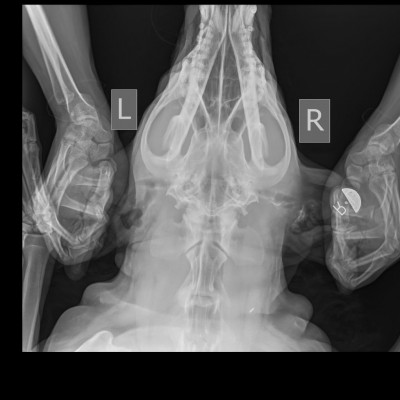

По локтю :

Крючковидный отросток фрагментирован, артрит.

Здесь по сути только НПВС курсами при обострении.

Это было понятно заранее.

С таким суставом Блэку жить.

Сустав отреагировал на 10 дней антибиотика лучше, чем на хондропротектор. Хромота заметно снизилась:))))